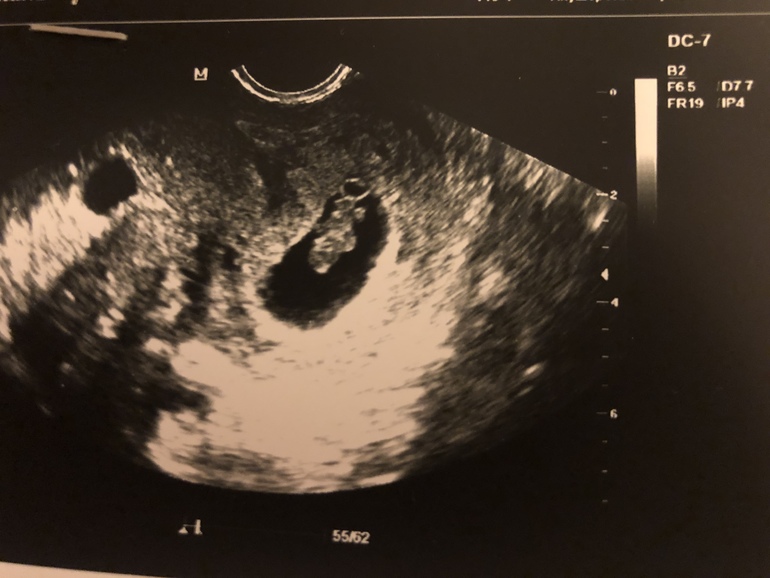

Узи в 8,1 недель

СЕГОДНЯ :

Ктр 16,6 мм( соответствует 8,1нед)

Пя 40 мм

Сб 176 уд/ мин

Жм 5,4

У малыша уже есть ножки , ручки маленькие 😍.Узист сказала - похож на медвежонка .

на фото медвежонок головой вниз лежит😍